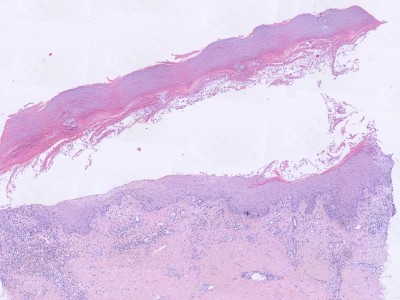

Klinisch beeld:Kleine tot grote spongiotische

vesikels tot bullae, vooral op laterale zijden vingers beide handen, handpalmen

en voetzolen (zelden). Het kan acuut zijn, recidiverend, of chronisch. Gaat

gepaard met jeuk of branderigheid. Bij warm weer is het erger. Soms treedt secundaire

infectie op met als mogelijk complicatie erysipelas of lymfangitis. Bij chronische

varianten kan ook nageldystrofie optreden.

PA:

het histologisch beeld in de fase dat er klinisch vesikels zijn is dat van een

acuut eczeem met spongiose.